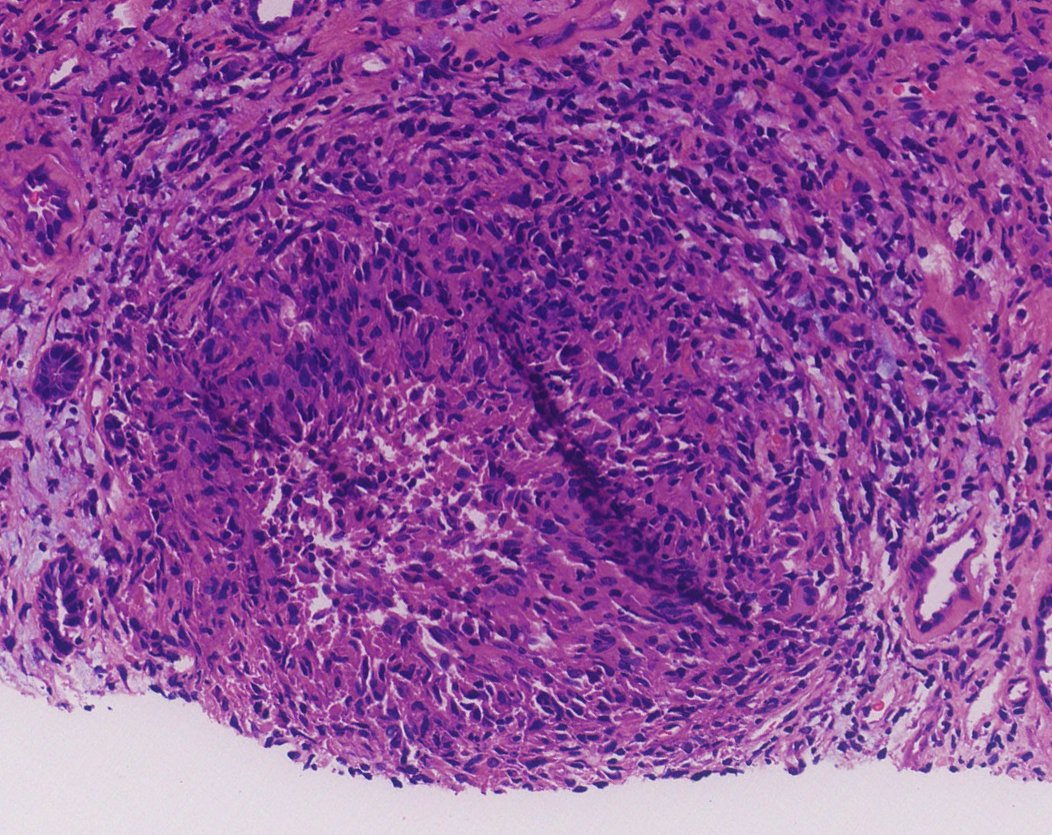

BK nephropathy Clues: - Heavy but focal tubulointerstitial inflammation - Increased plasma cells - Viral cytopathic change - Features of CNI toxicity ->over immunosuppression (isometric vacuolization shown here) -SV40 IHC confirmatory #renalpath #pathtwitter #nephrology